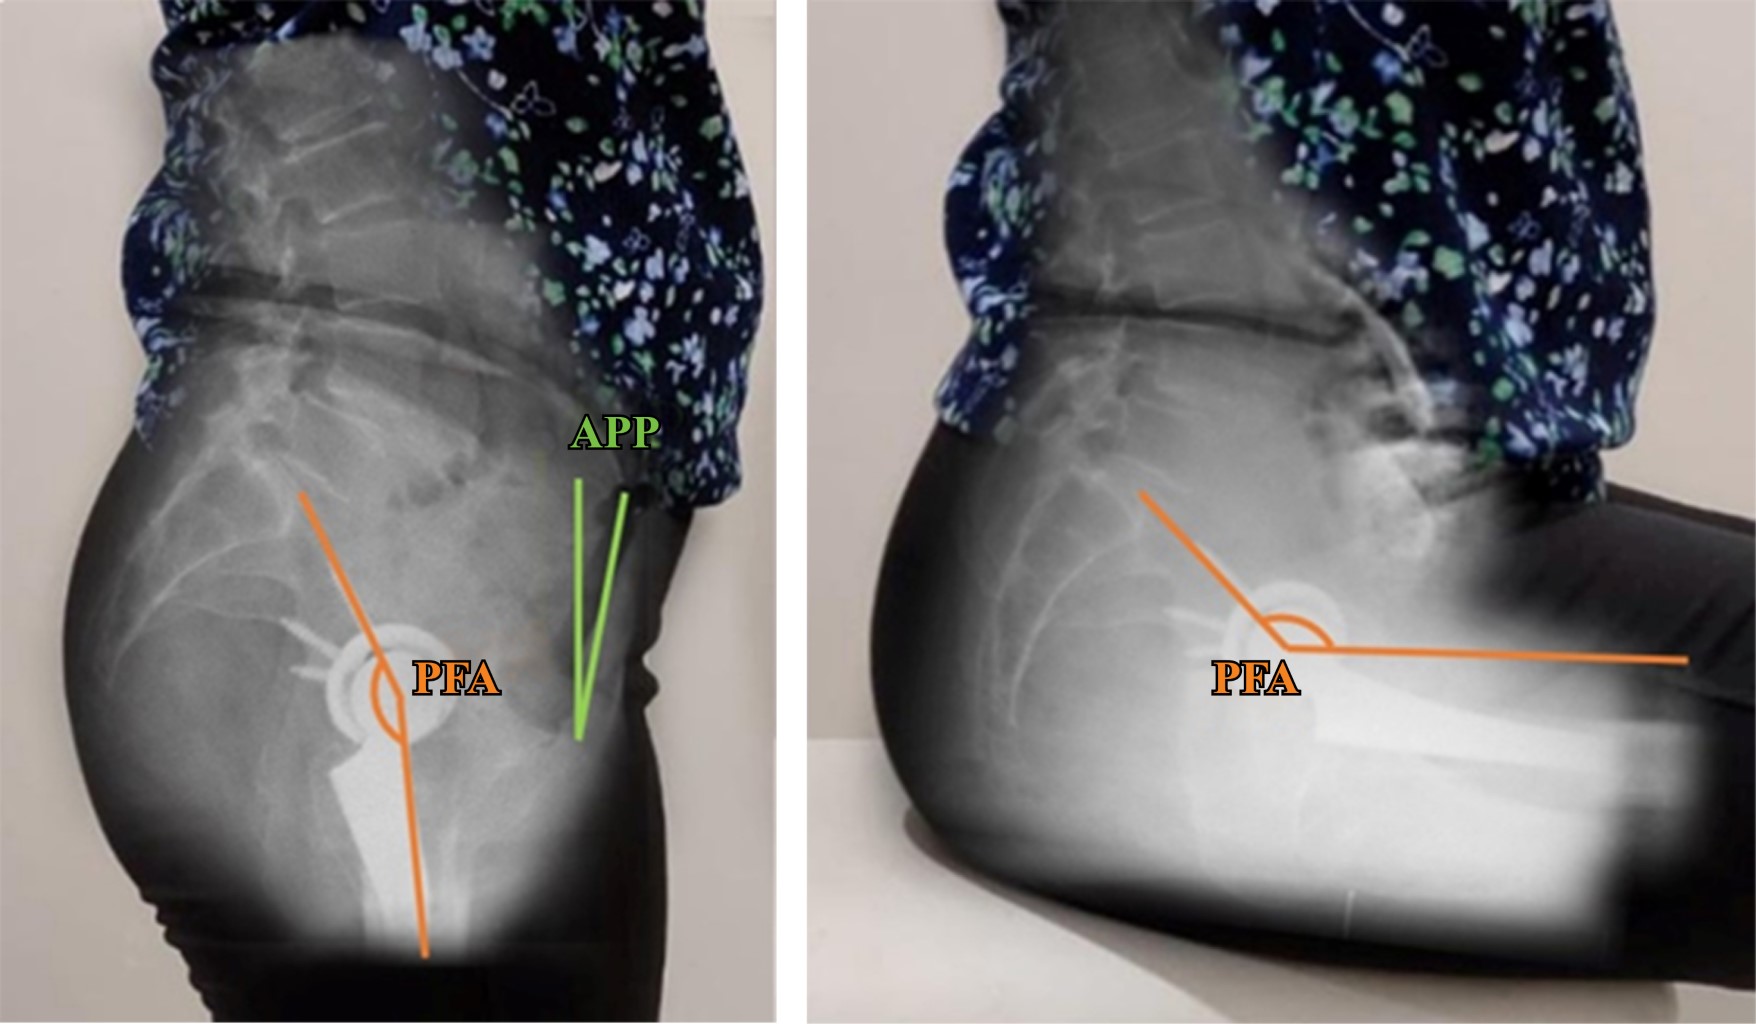

Introduction: the analysis of spinopelvic imbalance in patients undergoing total hip arthroplasty has gained significance in recent years, being recognized as a risk factor for instability. Few reports exist regarding the prevalence of spinopelvic alterations in Latin American literature. The aim of this study is to determine the frequency of spinopelvic imbalance in our patients and to associate them with functional outcomes. Material and methods: 29 patients who underwent total hip arthroplasty using a lateral approach (32 arthroplasties) were included. All patients completed clinical outcome questionnaires preoperatively. Twelve months after surgery, they underwent anteroposterior pelvic and lateral pelvic X-rays, both standing and sitting, and clinical outcome questionnaires were completed. The radiographic parameters examined were: pelvic incidence, lumbar lordosis, sacral slope, anterior pelvic plane and pelvic femoral angle. Functional outcome was assessed with the Harris Hip Score and WOMAC scales. Patients were classified according to their spinopelvic alteration and statistical analysis was performed to identify significant differences between the groups and the correlation with functional outcomes. Results: there was a high frequency of spinopelvic balance alterations (46.8%); 6.2% (n = 2/32) presented isolated spinal stiffness (group 1B), 37.5% (n = 12/29) spinal deformity without spinal stiffness (group 2A) and 3.1% (n = 1/29) spinal deformity associated with stiffness (group 2B). We found no improvement in HHS and WOMAC scores in the groups with spinal stiffness (1B and 2B) (p = 0.98 y 0.15). There is association between spinal stiffness (ΔSS < 10°) and poor functional outcomes (p = 0.02). Conclusions: the frequency of spinopelvic balance alterations was high. While there was no observed rise in prosthetic dislocations, the existence of spinal stiffness, defined by a ΔSS of less than 10°, was associated to poor outcomes on functional scales.

Figure 1